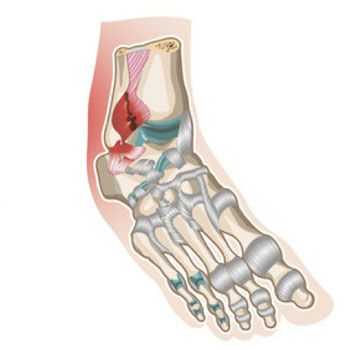

Разрыв связок происходит, когда подворачиваются ноги внутрь. При этом нагрузка на наружные связки сустава значительно увеличивается. В определенных случаях возможен перелом костей, которые формируют сустав.

Иногда растяжение связок голеностопного сустава сопоставляют с повреждениями, проявляющимися в результате подворачивании стопы. Однако в этом случае ошибочно говорить о растяжении, поскольку имеют место кровоподтеки и отечность. В момент получения травмы возникают разрывы в области связочного аппарата. В свою очередь, при растяжении нарушается целостность некоторых волокон, но функциональные характеристики остаются без изменений.

При более серьезных травмах может наблюдаться полный разрыв связок голеностопного сустава. При этом проявляются признаки, идентичные перелому костей. Больной утрачивает способность передвигаться, поскольку ощущает сильный болевой синдром и невозможность наступать на конечность. Подобные симптомы обусловлены изменением анатомического соотношения составных частей сустава. К числу характерных черт недуга также относится быстрое распространение гематомы и отечности на всю площадь лодыжки.